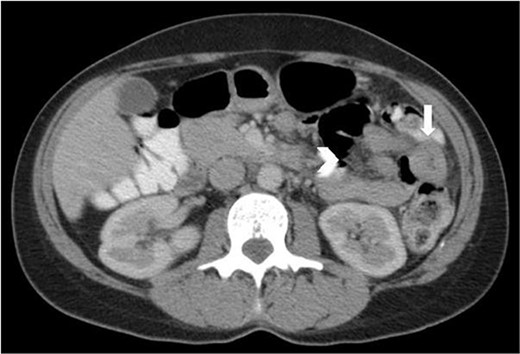

On retrospective review of this patient’s clinical course, she had presented to the emergency department many times with abdominal pain. Lipase was never elevated. On one presentation, a few years prior to her laparoscopy, a CT revealed a short segment of thickened jejunum in the left upper quadrant with associated mesenteric enhancement (Fig. 5); this was reported as a non-specific finding. C-reactive protein at this time was mildly elevated.

Axial CT abdomen and pelvis with portal venous phase and oral contrast, demonstrating a short segment of thickened jejunum (arrow) in the left upper quadrant with associated mesenteric enhancement (arrow head).